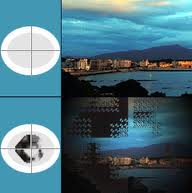

La mayoría son asintomáticos, pero pueden provocar una pérdida significativa del campo visual a través de episodios vasculares agudos y mecanismos de progresión lenta.

El aumento de las drusas exacerba la tensión mecánica en las delicadas estructuras contenidas dentro del canal prelaminar escleral, en ocasiones, conduce a una pérdida significativa del campo visual.

La pérdida del campo visual va desde 24% a 87% y por lo general progresa a un ritmo de alrededor del 1,6% al año.